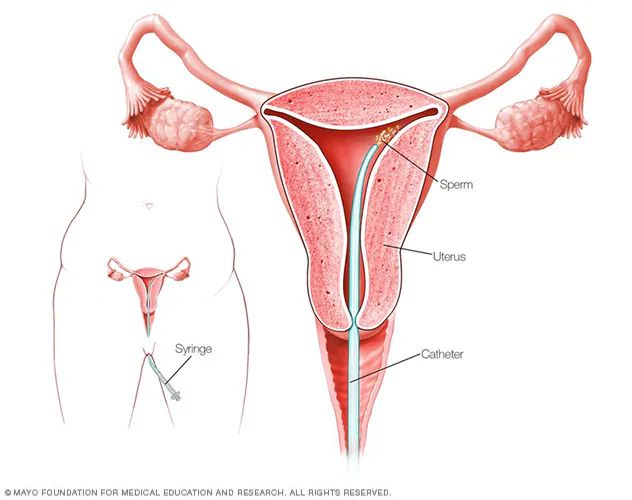

An Intrauterine Insemination Procedure (IUI) is a type of fertility treatment where sperm is directly placed into a woman’s uterus for fertilization. The main objective of IUI is to boost the chances of pregnancy by increasing the number of healthy sperm that reach the fallopian tubes during the woman’s fertility period.

Artificial insemination, or intrauterine insemination (IUI), is a common reproductive procedure used to assist individuals and couples who are having trouble becoming pregnant. It is a minimally invasive process to improve the chances of fertilisation by inserting sperm directly into the uterus during ovulation. IUI is often one of the first treatments suggested for minor reproductive difficulties or infertility that cannot be explained. IUI gives hope to many parents with its simple procedure and demonstrated efficacy.

To ascertain the best timing for IUI, the woman’s ovulation is tracked using transvaginal ultrasound.

A procedure known as “sperm wash” is used to concentrate the high-quality sperm while eliminating dead or sluggish-moving sperm cells.

Insemination

A tiny catheter is used to inject the healthy sperm into the woman’s uterus.